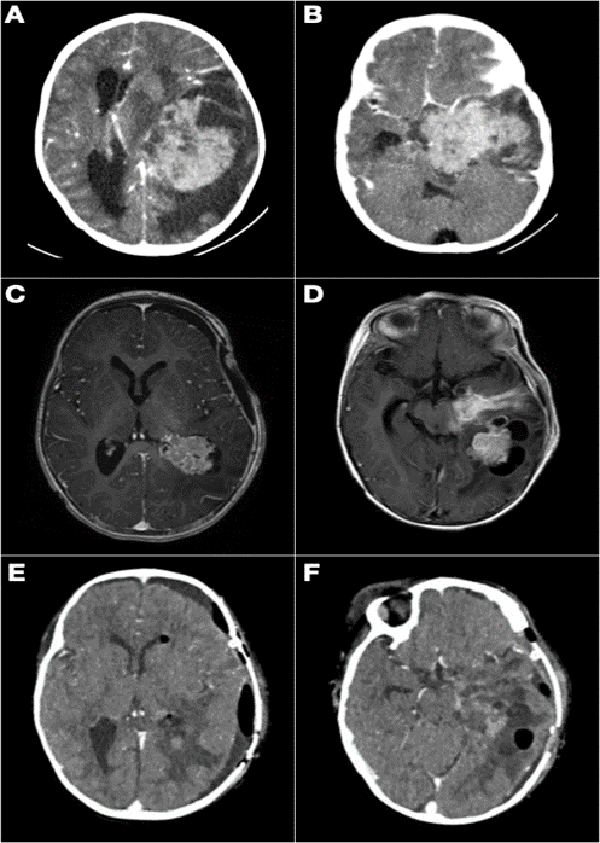

Analizando por separado los resultados de anatomías patológicas vemos que los ATRT, meduloblastomas y ependimomas tuvieron una supervivencia del 32% a los 5 años (Figuras 3 y 4) y los pacientes con tumores embrionarios, PNET, carcinomas y papilomas atípicos de plexos coroideos y pineoblastomas presentaron una mortalidad del 100% a los 5 años (Figuras 5 y 6). Por otro lado, los papilomas de plexos coroideos, lesiones más frecuentes en el grupo 1, tuvieron un 100% de supervivencia a los 10 años, al igual que los astrocitomas y gliomas de bajo grado (Figuras 7 y 8).

Figura 8: A y B) Paciente de 21 meses de vida, sexo femenino, que presentó hemiparesia faciobraquiocrural derecha, vómitos y deterioro del sensorio, TC de cerebro con contraste EV, lesión supra e infratentorial, con gran efecto de masa con compresión del tronco del encéfalo. Se realizó cirugía de exploración y exéresis parcial. Anatomía patológica informó papiloma de plexos coroideos. C y D) IRM de cerebro con contraste EV que evidenció resto tumoral intraventricular y en relación a cisternas peri mesencefálicas. Se realizó re exploración del tumor. E y F) Imagen por TC de cerebro con contraste EV postquirúrgica inmediata que evidenció exéresis total.